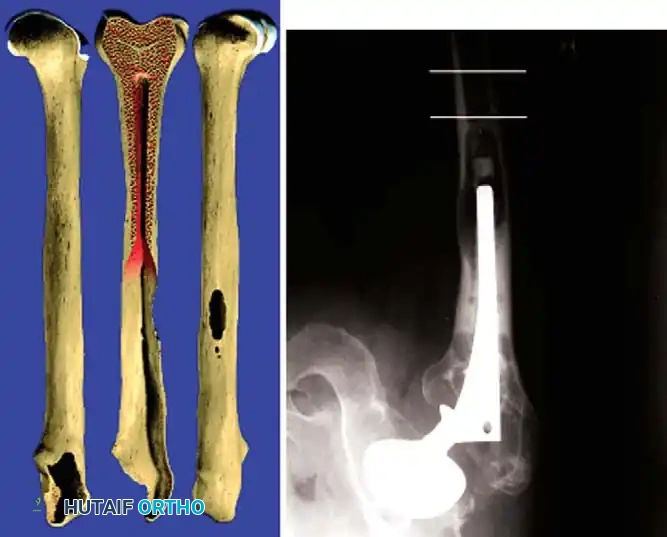

Femoral Reconstruction

Femoral bone loss dictates stem selection. The fundamental biomechanical principle of femoral revision is to achieve rigid fixation in healthy, diaphyseal bone, bypassing the proximal deficiency by a minimum of two cortical diameters (typically 4-6 cm).

Implant Options:

1. Fully Porous-Coated Cylindrical Stems: Excellent long-term survivorship in Type I and II femoral defects. They rely on extensive diaphyseal scratch fit.

2. Modular Fluted Tapered Stems: The modern workhorse for severe (Type III and IV) defects. The flutes provide rotational stability, while the 2-to-3 degree taper achieves axial stability via three-point fixation in the diaphysis. Modularity allows independent adjustment of version, offset, and leg length after the distal stem is rigidly seated.

Pitfall: When seating a diaphyseal-engaging stem, prophylactic cerclage cabling of the distal femur is highly recommended to prevent catastrophic intraoperative splitting of the diaphysis during final impaction.